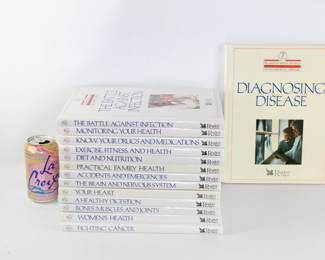

1126 - Home Medical Library